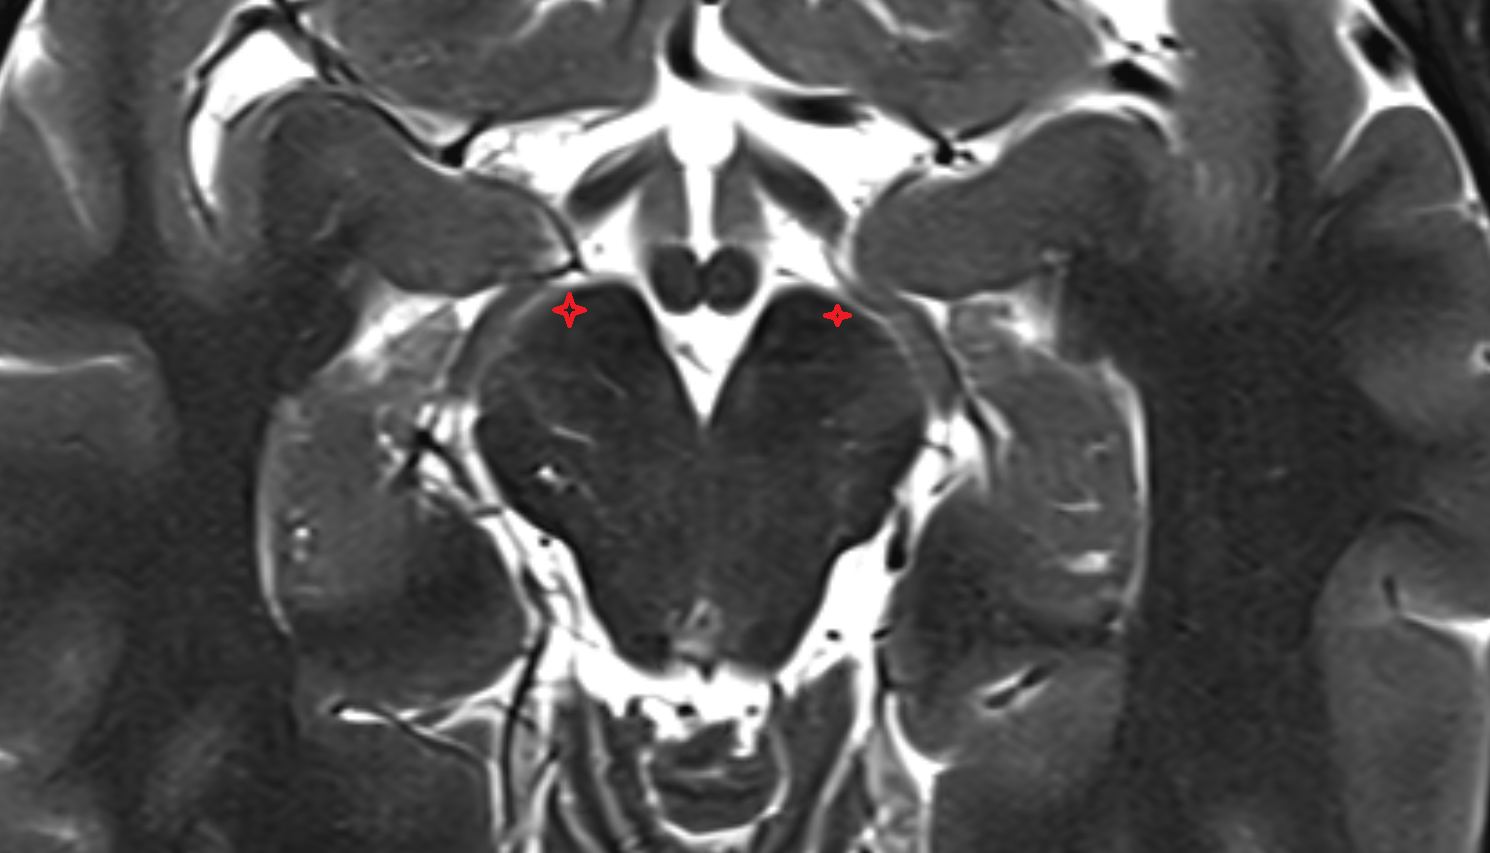

- Dentate nucleus